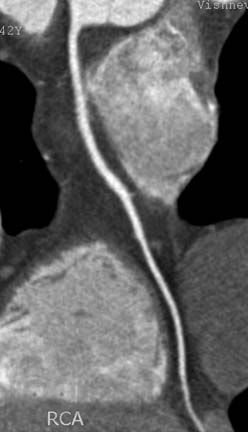

Достоинствами метода МСКТ-КГ являются неинвазивность и возможность оценить не только просвет коронарной артерии, проходимость аортокоронарных шунтов и стентов, но и состояние стенки сосуда, структуру атеросклеротической бляшки, а также возможность визуализации полостей сердца, миокарда и анатомических структур в зоне исследования.